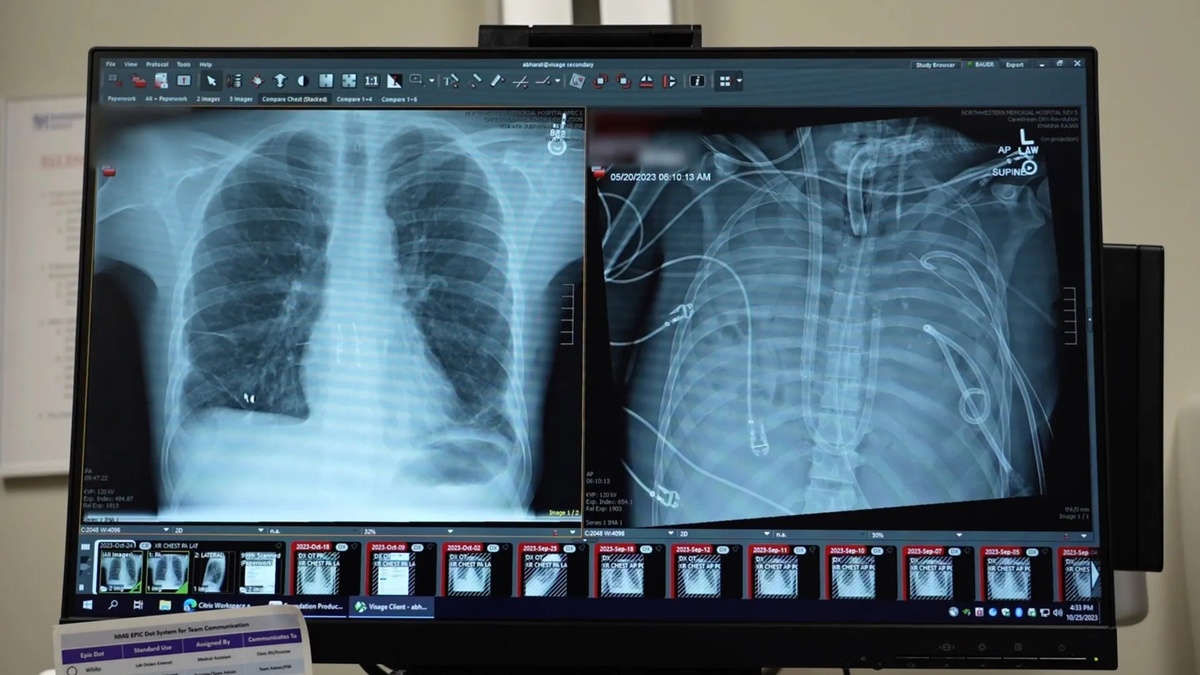

🫁 Реальность круче любого фильма! В Northwestern Medicine врачи совершили невозможное: пациент прожил двое суток вообще без легких. 33-летний мужчина умирал от последствий гриппа и пневмонии — его органы буквально «плавились», отравляя кровь продуктами распада. ⚡️ Чтобы спасти парня, хирурги решились на отчаянный шаг: они полностью удалили гниющие ткани и подключили тело к системе «искусственного легкого». Это позволило очистить организм от токсичной инфекции и дождаться донора. Пока в грудной клетке была пустота, аппарат насыщал кровь кислородом и поддерживал работу сердца. 🏆 Итог: успешная двойная трансплантация и полное восстановление. Теперь мы знаем, что критическое поражение легких — это не приговор. Медицина будущего уже здесь, и она дает шанс там, где раньше была неизбежная смерть. #здоровье #новости #медицина #биотехнологии #наука #трансплантация #технологии

🫁 Реальность круче любого фильма! В Northwestern Medicine врачи совершили невозможное: пациент прожил двое суток вообще без легких. 33-летний мужчина умирал от последствий гриппа и пневмонии — его органы буквально «плавились», отравляя кровь продуктами распада.

⚡️ Чтобы спасти парня, хирурги решились на отчаянный шаг: они полностью удалили гниющие ткани и подключили тело к системе «искусственного легкого». Это позволило очистить организм от токсичной инфекции и дождаться донора. Пока в грудной клетке была пустота, аппарат насыщал кровь кислородом и поддерживал работу сердца.

🏆 Итог: успешная двойная трансплантация и полное восстановление. Теперь мы знаем, что критическое поражение легких — это не приговор. Медицина будущего уже здесь, и она дает шанс там, где раньше была неизбежная смерть.